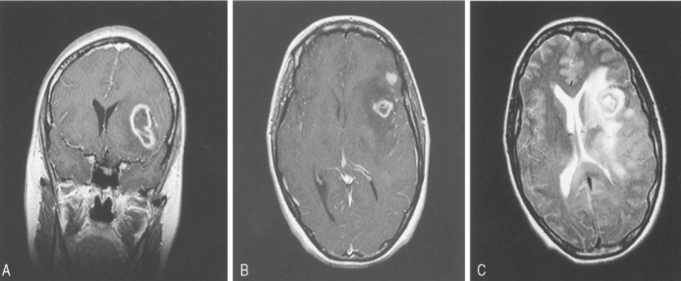

星形细胞瘤也是一种胶质细胞肿瘤,起源于一种叫做星形细胞的结缔组织细胞。星形细胞瘤是儿童脑瘤中较常见的类型,其比较常见的位置就是小脑,在那里它们被称为小脑星形细胞瘤。这些肿瘤通常引起颅内压升高、头痛和呕吐。走路和协调能力也会有问题,还有复视。

3、髓母细胞瘤:髓母细胞瘤是一种位于小脑中线附近的PNET。该肿瘤生长迅速,常阻塞脑脊液(脑脊液,可浸润大脑和脊髓)的引流,引起颅内压增高相关症状。髓母细胞瘤细胞可以扩散(转移)到中枢神经系统的其他区域,特别是在脊髓周围。

小脑肿瘤的临床表现与肿瘤的大小、位置和患者年龄有关。头痛和共济失调是小脑肿瘤患者常见的两种症状。头痛可能是由肿瘤压迫或脑积水引起的。通常发生于枕部,伴有恶心、呕吐,偶尔伴有颈部僵硬。有些病人可能会感到眩晕。小脑中线病变可引起躯干性共济失调,小脑半球病变可引起阑尾性共济失调,但其表现往往很细微。检查还可发现眼球震颤、张力减退,以及脑干压迫引起的颅神经和皮质脊髓束征。在开始扁桃体突出时,可能会出现头部偏出病变。